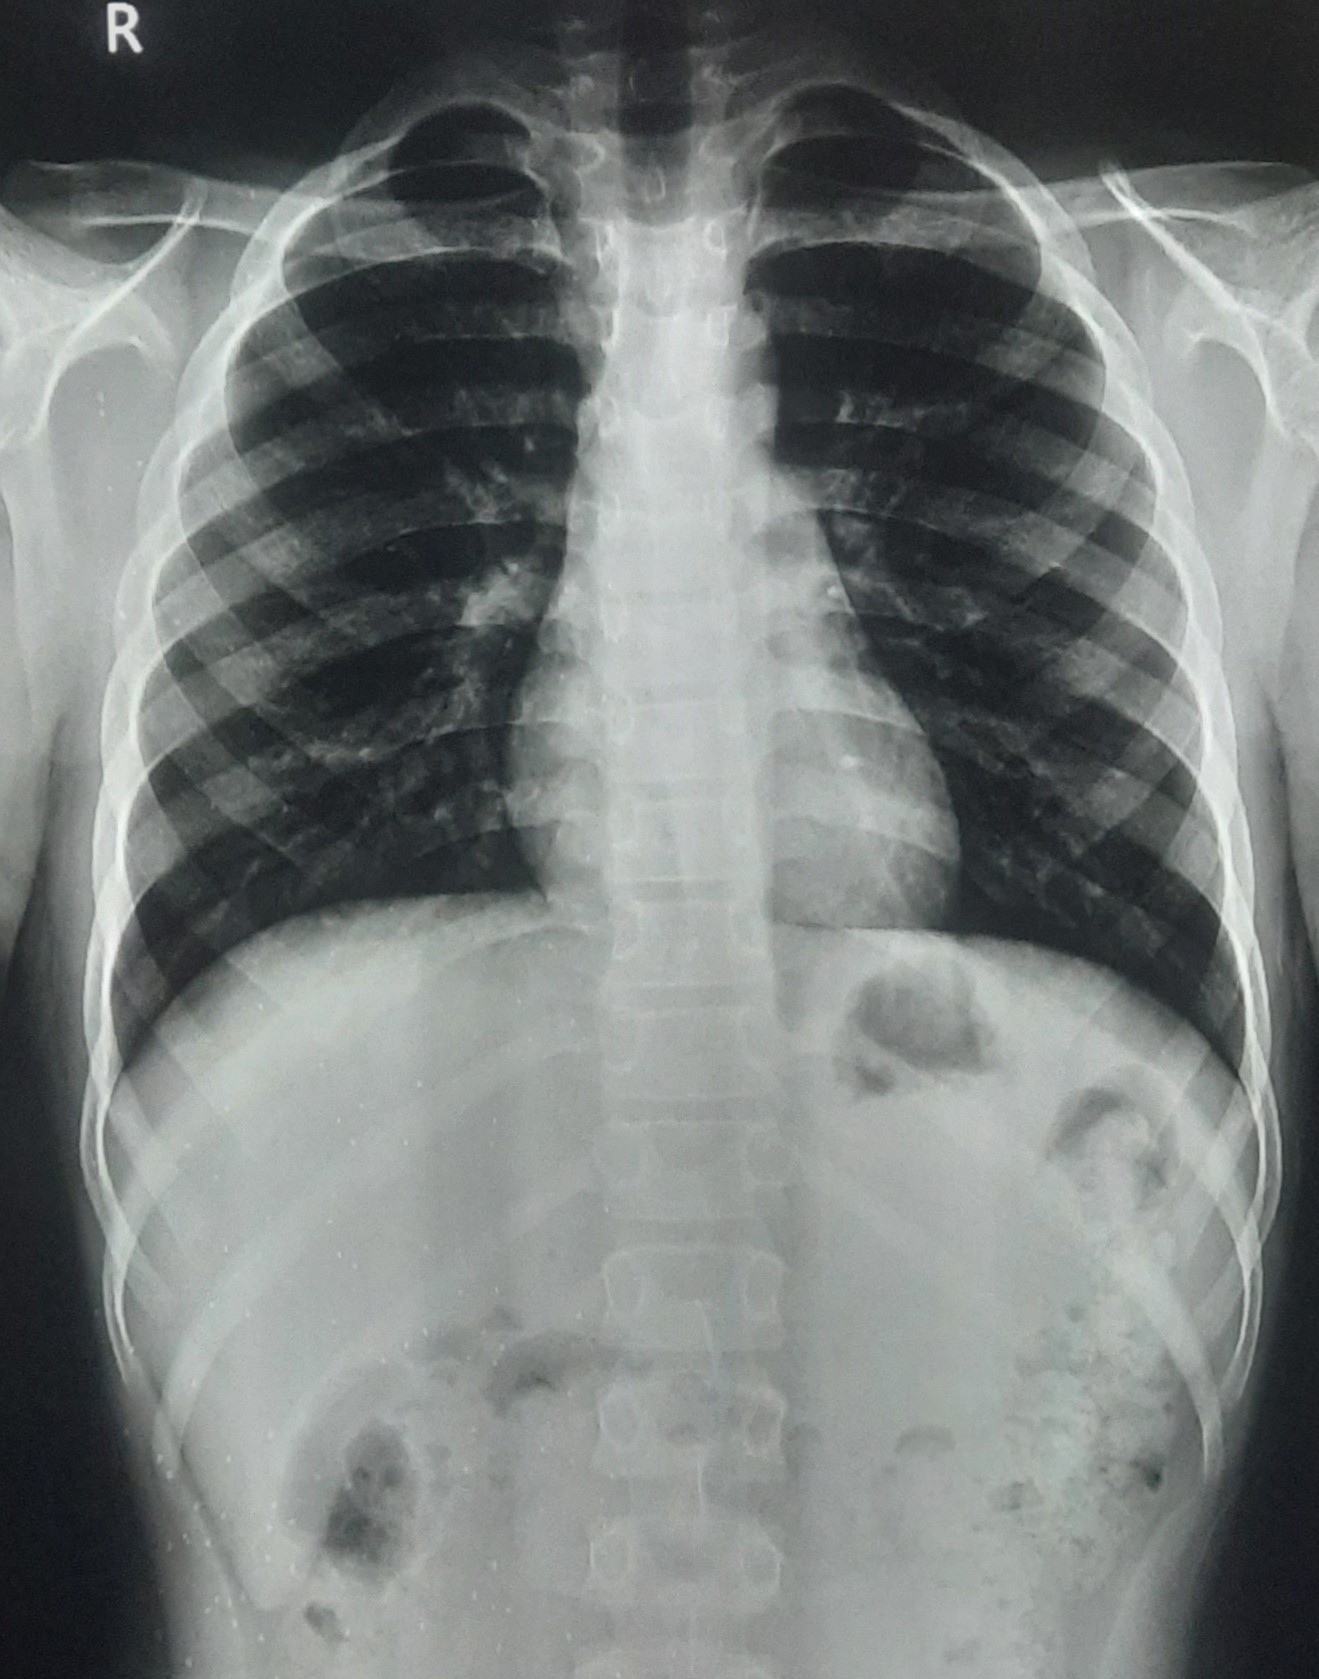

| 301 | IGGMC, Nagpur, Nagpur | P2 | 29-4171 | Gaurav Ambade | Consent taken on Paper | 27 Yrs. |

Provisional Diag : Pre-Employment Medical fitness

Final Diag : CxR- No Finding (Medical Fitness) |

Pure Normal Case (Cases with no complaint, NAD or medical fitness cases) | No significant abnormality seen in present chest X-ray | No abnormality visible on x-ray |